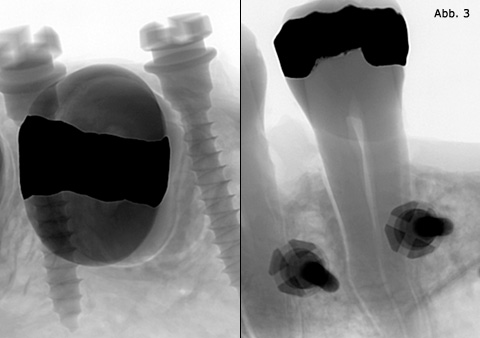

die Stabilität des Materials und die Platzverhältnisse am Insertionsort. Ersteres verlangt einen möglichst dicken (siehe PDF 2) und letzteres einen möglichst dünnen Durchmesser (Abb. 3). Für die sichere, in erster Linie mechanische Verankerung der Minischraube ist eine bestimmte Menge von Knochen zirkulär um die Schraube notwendig. Denn die Stabilität einer Minischraube im Knochen ergibt sich aus dem Durchmesser und nicht aus ihrer Länge.26, 27

Abb. 3 Der Platz zwischen den Wurzeln limitiert den Durchmesser.

Es gibt bis dato keine Studie, welche die tatsächlich minimal erforderliche Knochenstärke festgestellt hat. Die Angaben reichen von 0,5 bis zu 2 mm. Interradikulär gibt der Abstand zwischen den Wurzeln den Platz vor. Abzüglich der notwendigen Knochenstärke (mind. 0,5mm) ergibt sich daraus der maximale Durchmesser der Schraube. Publikationen von Poggio et al.22, Schnelle et al.23 und Costa et al.24–25 lassen Rückschlüsse über die vertikalen Platzverhältnisse, also das Gebiet zwischen Schmelz-Zement-Grenze und Mukogingivallinie, zu. Aus diesen Untersuchungen wird deutlich, dass der Durchmesser einer Minischraube nicht größer als 1,6mm sein sollte. Anderseits sollten 1,5mm nicht unterschritten werden, da ansonsten die Minischraube bei der Insertion brechen könnte (siehe PDF 2).